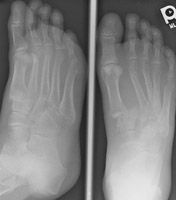

- Click on the image for a larger versionAAP radiograph of the forefoot. There is homolateral Lisfranc fracture-dislocation.